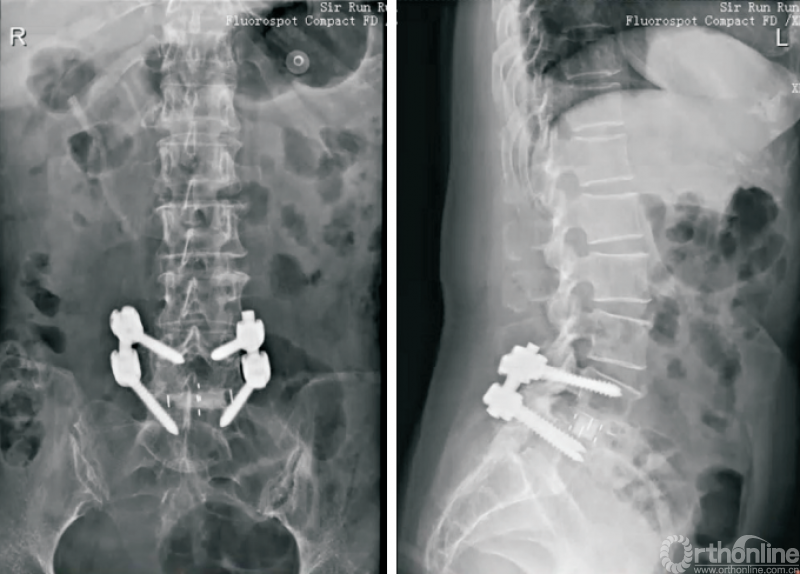

3.2 Stand⁃alone OLIF

尽管经典的OLIF手术能够有效解决众多腰椎失稳性疾病,但是术中变换体位、二期手术等因素限制了其应用。Stand-alone OLIF(图5)的概念也应运而生,Stand-alone OLIF能够避免椎旁肌肉等软组织的损伤,对于改善术后因肌肉剥离等引起的腰背部疼痛有一定的意义。

图5 Stand-alone OLIF

生物力学试验证明,侧方融合器可以有效重建脊柱的稳定性,也为Stand-Alone OLIF提供了理论依据[30-31]。ZHU等[32]通过比较Stand ⁃alone OLIF与PLIF两种手术方式治疗邻椎病,发现OLIF组术中出血量少,手术时间短,卧床休息时间短,住院时间短,且都能获得满意的融合效果。

UDBY等[33]回顾性研究对比Stand-alone前路融合与联合后路钉棒固定两种手术方式,结果发现,Stand-alone技术在ODI、VAS、手术时间、失血量和患者满意度等方面有显著优势。MANZUR等[34]回顾性分析了Stand-alone前路融合的融合率为88.6%,总体上获得了较高的融合率。因此,Stand-alone OLIF是一种有效的椎体间融合术式,且具有手术时间短、出血量少、患者满意度高、术后疼痛轻等优势。对于合适的患者选择Stand-alone OLIF,既能获得满意的疗效,又能尽可能减小损伤。

但是Stand-alone OLIF有其应用边界。对于骨密度降低[35]、术中终板损伤,术中前纵韧带损伤、冠状面失衡(C7铅垂线距离骶骨正中线>2cm)、动力位X线片显示动态不稳(过伸过屈位节段位移>3mm或角度变化>11°)、Ⅱ度退行性滑移、矢状面失衡(C7铅垂线距离骶骨后上角>2.5cm)、峡部裂滑移、邻椎病发生在原有融合节段远端、融合节段≥3个、Ⅱ~Ⅲ度关节突关节骨关节炎(关节突关节间隙狭窄,伴关节突明显增生肥大、硬化、骨赘增生、关节面破坏)等患者,建议联合内固定,以增强稳定性、降低翻修等的风险。

终板塌陷和融合器沉降(图6)是Stand-aloneOLIF的常见并发症,也是导致术后翻修的重要预测因素。融合器沉降与终板强度、手术操作以及解剖稳定性相关。终板硬化及形态平衡能够降低融合器沉降的发生率[36]

图6 OLIF术后融合器沉降